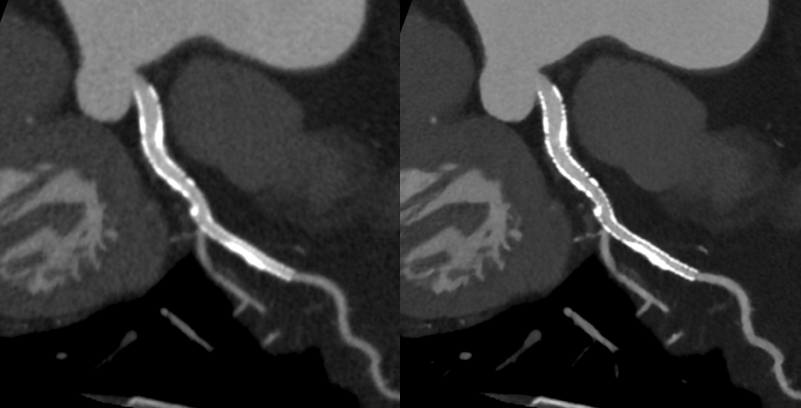

ステント症例:左の従来画像と比較して,右の高精細ディープラーニング画像では小さなステントの内部も明瞭に描出されています。

これまで、CTでは評価が難しいとされている冠動脈の強い石灰化部位やステント治療部位において、我々が考案した特殊な撮影(test bolus tracking法)および画像処理技術を用いて評価可能な画像を可能な限り提供しています。

通常の画像(左)に比べ、石灰化(白い部分)を除去した画像(右)では血管狭窄の有無が明瞭に評価できます。